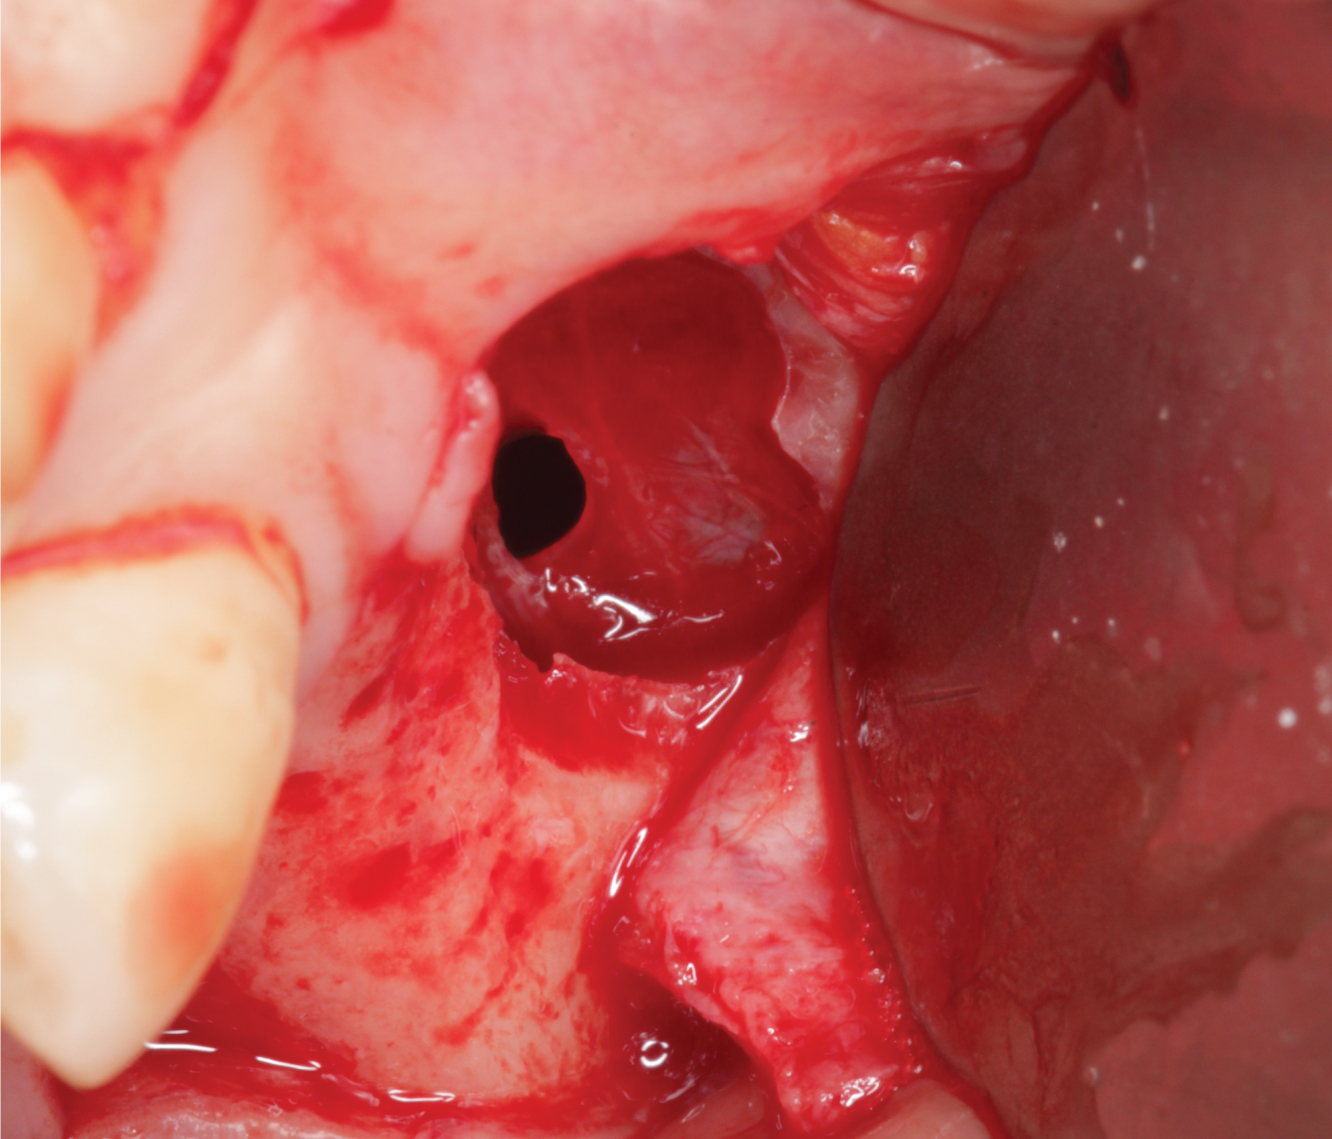

Director’s Clinical Cases

Director’s Clinical Cases